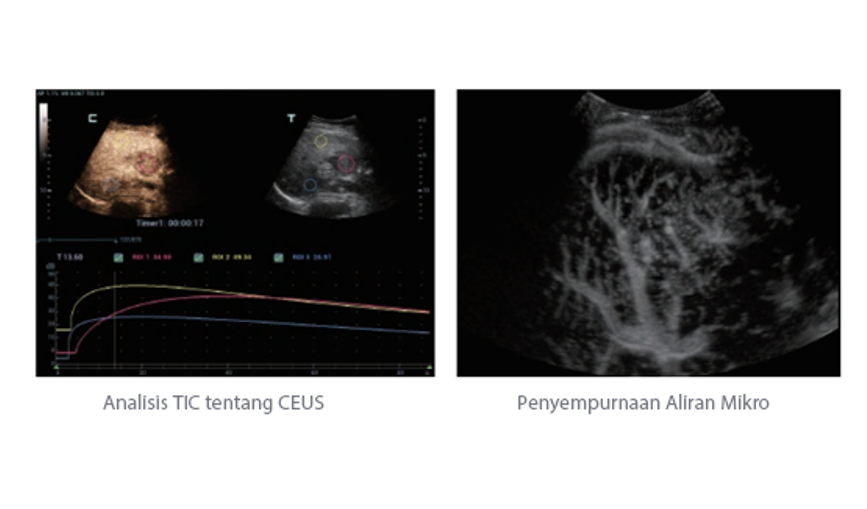

Selain kualitas gambar premium, Resona 7 juga meningkatkan kemampuan penelitian klinis dengan V Flow revolusioner untuk evaluasi hemodinamika vaskular, serta pengambilan penampang tercanggih dari rangkaian data 3D untuk diagnosis CNS pada janin. Kombinasi pengoperasian multisentuh berbasis gerakan yang paling intuitif dengan semua fitur klinis penting membuat Resona 7 menjadi gebrakan baru dalam inovasi ultrasound.